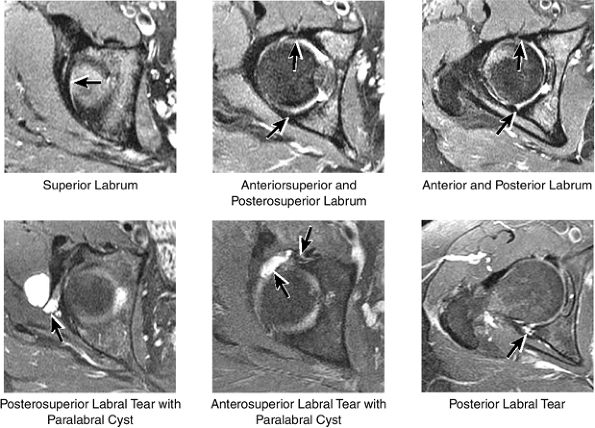

FIGURE 3.29 ● Normal axial anatomy of the hip. (A, B) At this level, the sciatic nerve can be seen exiting the sciatic foramen, deep to the piriformis muscle. Asymmetric enlargement of the piriformis muscle or masses in this region can cause impingement of the sciatic nerve, the so-called piriformis syndrome. (C, D) At this level the transition from the acetabular roof to the top of the femoral head is visualized. The thin arc of dark signal along the lateral margin of the acetabular roof represents the superior margin of the labrum. High signal in the superior labrum can be identified as a labral tear, and accompanying paralabral cysts are commonly identified extending superficial to the labrum. (E, F) The anterior labrum and the posterior labrum on axial images are identified as dark-signal triangles at the lateral margin of the acetabuli. Labral tears present as linear or irregular fluid signal extending through the substance of the labrum, or as expansion of the labrum by fluid signal extending to the surface of the labrum. Fluid signal interposed between the labrum and the acetabulum at the labral attachment indicates labral detachment.(G, H) Tendinosis of the gluteus medius and minimus insertions on the greater trochanter is visualized as thickening and increased signal of the tendons. Trochanteric bursitis can be identified either superficial or deep to the gluteus medius and minimus insertions. (I, J) A fluid collection anteromedial or anterolateral (or both) to the iliopsoas tendon is compatible with iliopsoas bursitis. Occasionally, iliopsoas bursitis may be present adjacent to an anterior labral tear, in which case it may be difficult to distinguish from a paralabral cyst. (K, L) The common hamstring origin on the ischium comprises the biceps femoris and semitendinosus tendons. The common hamstring tendon is a frequent site for tendinosis or partial tears, and the pathology is commonly symmetric.